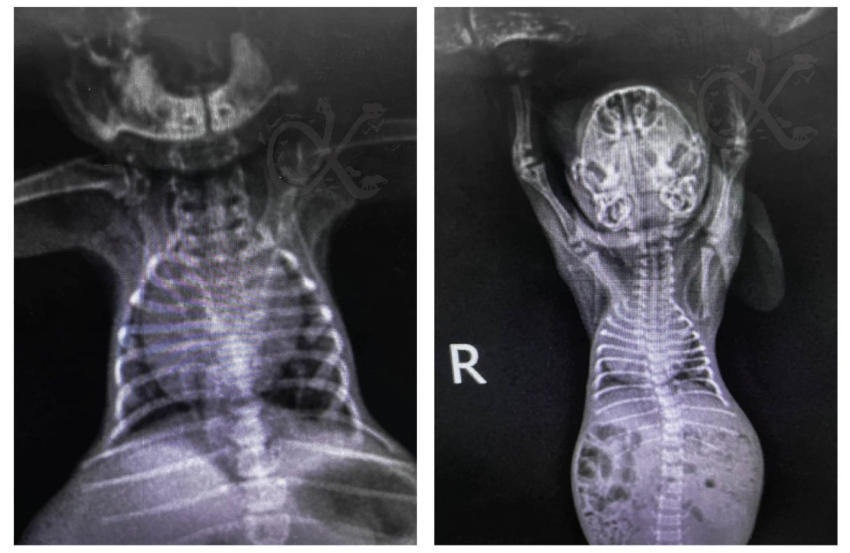

X-rays are the first line of defense in identifying an enlarged heart. Vets look for several key indicators:

Lung Congestion: The X-ray can also show if the heart enlargement is causing fluid buildup in the lungs (pulmonary edema) or pleural effusion, which are signs of congestive heart failure.

Cardiac Silhouette: Vets assess the overall shape and size of the heart "shadow" to see if specific chambers (like the left atrium) are bulging.